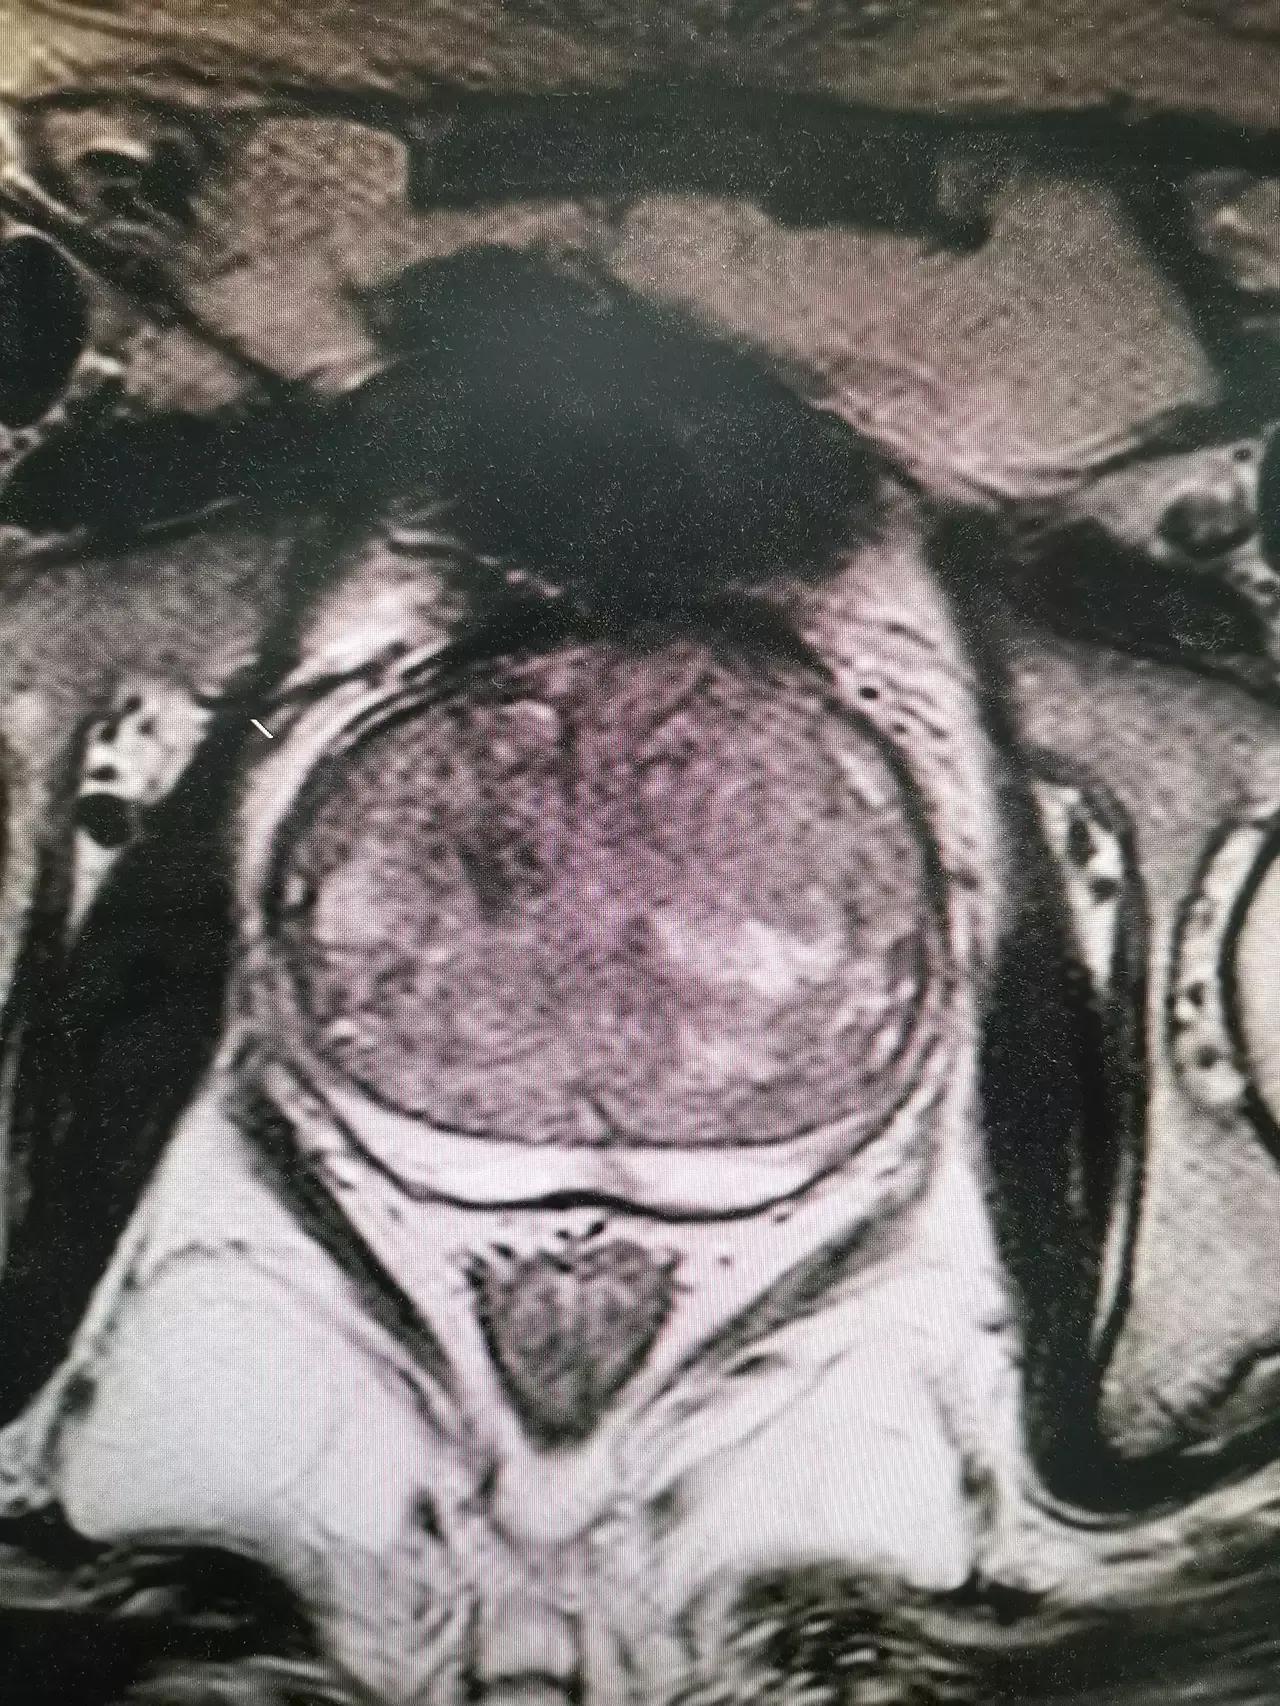

6、前列腺癌

早期前列腺癌一般不会有明显的临床症状,对于移行带部位的肿瘤或者肿瘤刺激膀胱三角区部位,就会有尿频的症状。对于前列腺癌的治疗目前多主张手术治疗了。